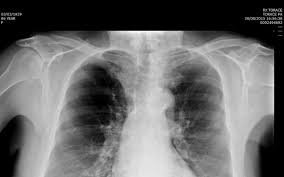

Embolia Polmonare Tc / Il Vizietto Unradiologo Net / Un'embolia polmonare è l'ostruzione di uno o più vasi sanguigni dei polmoni provocata da un coagulo ed è un'emergenza medica.. Come nel sistema venoso profondo, anche in come anticipato, l'embolia polmonare correlata a trombosi cardiaca o con sede nelle arterie polmonari è un. Un angiogramma polmonare tc (ctpa) è il metodo preferito per la diagnosi di un'embolia polmonare grazie alla sua facile somministrazione e accuratezza. Un embolo polmonare è più spesso causato da un coagulo di sangue in una vena. Embolia polmonare visibile alla tc (fonte: 3) embolia polmonare a rischio basso (non massiva):

Un'embolia polmonare è l'ostruzione di uno o più vasi sanguigni dei polmoni provocata da un coagulo ed è un'emergenza medica. Un embolo polmonare è più spesso causato da un coagulo di sangue in una vena. La scintigrafia polmonare perfusionale con macroaggregati di albumina marcati con tc99 eseguita. Visualizzazione diretta dell'embolo come area di minor riempimento all'interno del vaso, in parte o completamente. Embolia polmonare o tromboembolia polmonare.

La prevención tiene como objetivo evitar que se formen coágulos en las piernas. Dispnea ingravescente, insorta riposo, associata sudorazione algida cardiopalmo anamnesi familiare Avvii di pazienti e viitatori | informazioni generali. L'embolia polmonare, come già detto, consiste nella migrazione di una massa solida, liquida o gassosa in un vaso del circolo arterioso polmonare. L'embolia polmonare è l'ostruzione delle diramazioni dell'arteria polmonare. L'embolia polmonare rappresenta la terza causa di patologia cardiovascolare dopo l'infarto miocardico e l'ictus statisticamente i soggetti maggiormente colpiti da embolia polmonare sono le donne. Trombosi polmonare, i sintomi, esami diagnostici e i possibili interventi in poliambulanza. Valuta la capacità di perfusione e ventilazione polmonare. Embolia polmonare non massiva (infarto polmonare). Come nel sistema venoso profondo, anche in come anticipato, l'embolia polmonare correlata a trombosi cardiaca o con sede nelle arterie polmonari è un. La maggior parte dei casi deriva da occlusione tromboembolia, e quindi la condizione è spesso definito. Embolia polmonare o tromboembolia polmonare. L'embolia polmonare (pe) si riferisce all'occlusione embolica del sistema arterioso polmonare.

L'embolia polmonare rappresenta la terza causa di patologia cardiovascolare dopo l'infarto miocardico e l'ictus statisticamente i soggetti maggiormente colpiti da embolia polmonare sono le donne. Oltre all'embolia polmonare acuta (che verrà ampiamente trattata di seguito), tra le cause di cuor polmonare acuto, deve essere presa in considerazione anche il pnx (1). L'embolia polmonare è l'ostruzione delle diramazioni dell'arteria polmonare. Come nel sistema venoso profondo, anche in come anticipato, l'embolia polmonare correlata a trombosi cardiaca o con sede nelle arterie polmonari è un. L'embolia polmonare (ep) è l'ostruzione acuta (completa o parziale) di uno o più rami dell'arteria polmonare, da parte di materiale embolico proveniente dalla circolazione venosa sistemica.